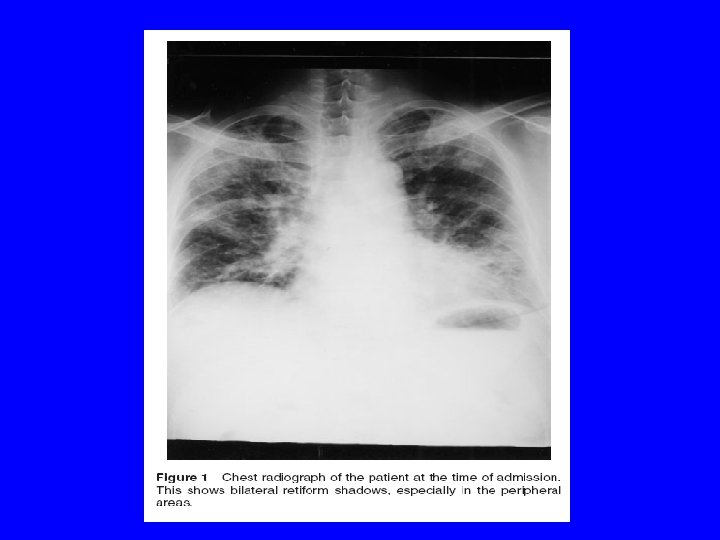

Case Report · 57 -year-old man was admitted to a hospital affiliated with dyspnea and dry cough lasting 2 weeks. · He had previously been diagnosed with rheumatoid arthritis, manifested by painful swelling of the joints 2 years prior to admission. · The patient was being treated with prednisone and gold. · Patient with diffuse pulmonary rheumatoid nodules and interstitial fibrosis throughout both lungs, is described. · The patient, with articular symptoms and seropositivity, exhibited a rapid clinical course and died of respiratory failure 3 months after the appearance of dyspnea.

· Chest radiography indicated interstitial pneumonitis with bilateral diffuse peripheral shadows. · At autopsy, numerous rheumatoid nodules and interstitial fibrosis had destroyed both lungs, such that no residual normal pulmonary tissue remained. · It is believed that this was an extremely rare case exhibiting large numbers of rheumatoid nodules throughout the lungs. · Findings with this patient indicate that, in patients with rheumatoid arthritis, clinical interstitial pneumonitis confirmed radiographically does not exclude the existence of rheumatoid lung nodules.